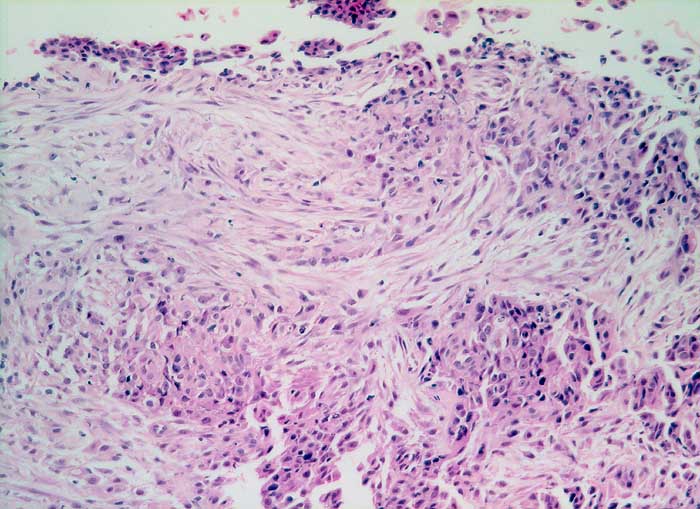

Entscheidend für die Diagnose eines malignen Mesothelioms sind maligne Zellen, die aussehen wie Mesothelzellen. Typisch ist ein Kontinuum von gutartigen, abnormen und malignen mesothelialen Zellen. Die Tumorzellen bilden polyzyklisch begrenzte papilliforme Verbände oder sitzen einem homogenen Matrixkern auf. Zellkannibalismus und lange Zellketten (Indian Files) sind häufig bei Mesotheliomen und selten in gutartigen Ergüssen. Die einzelnen malignen Zellen sind grösser und variabler als gutartige Mesothelien. Oft trifft man auf grosse und mehrkernige Tumorzellen. Das Zytoplasma von Mesotheliomen ist auffallend dicht ,anders als das eher helle Zytoplasma von Adenokarzinomen.

Wichtig für die Diagnosestellung ist der Einbezug klinischer und allenfalls immunzytochemischer Befunde.